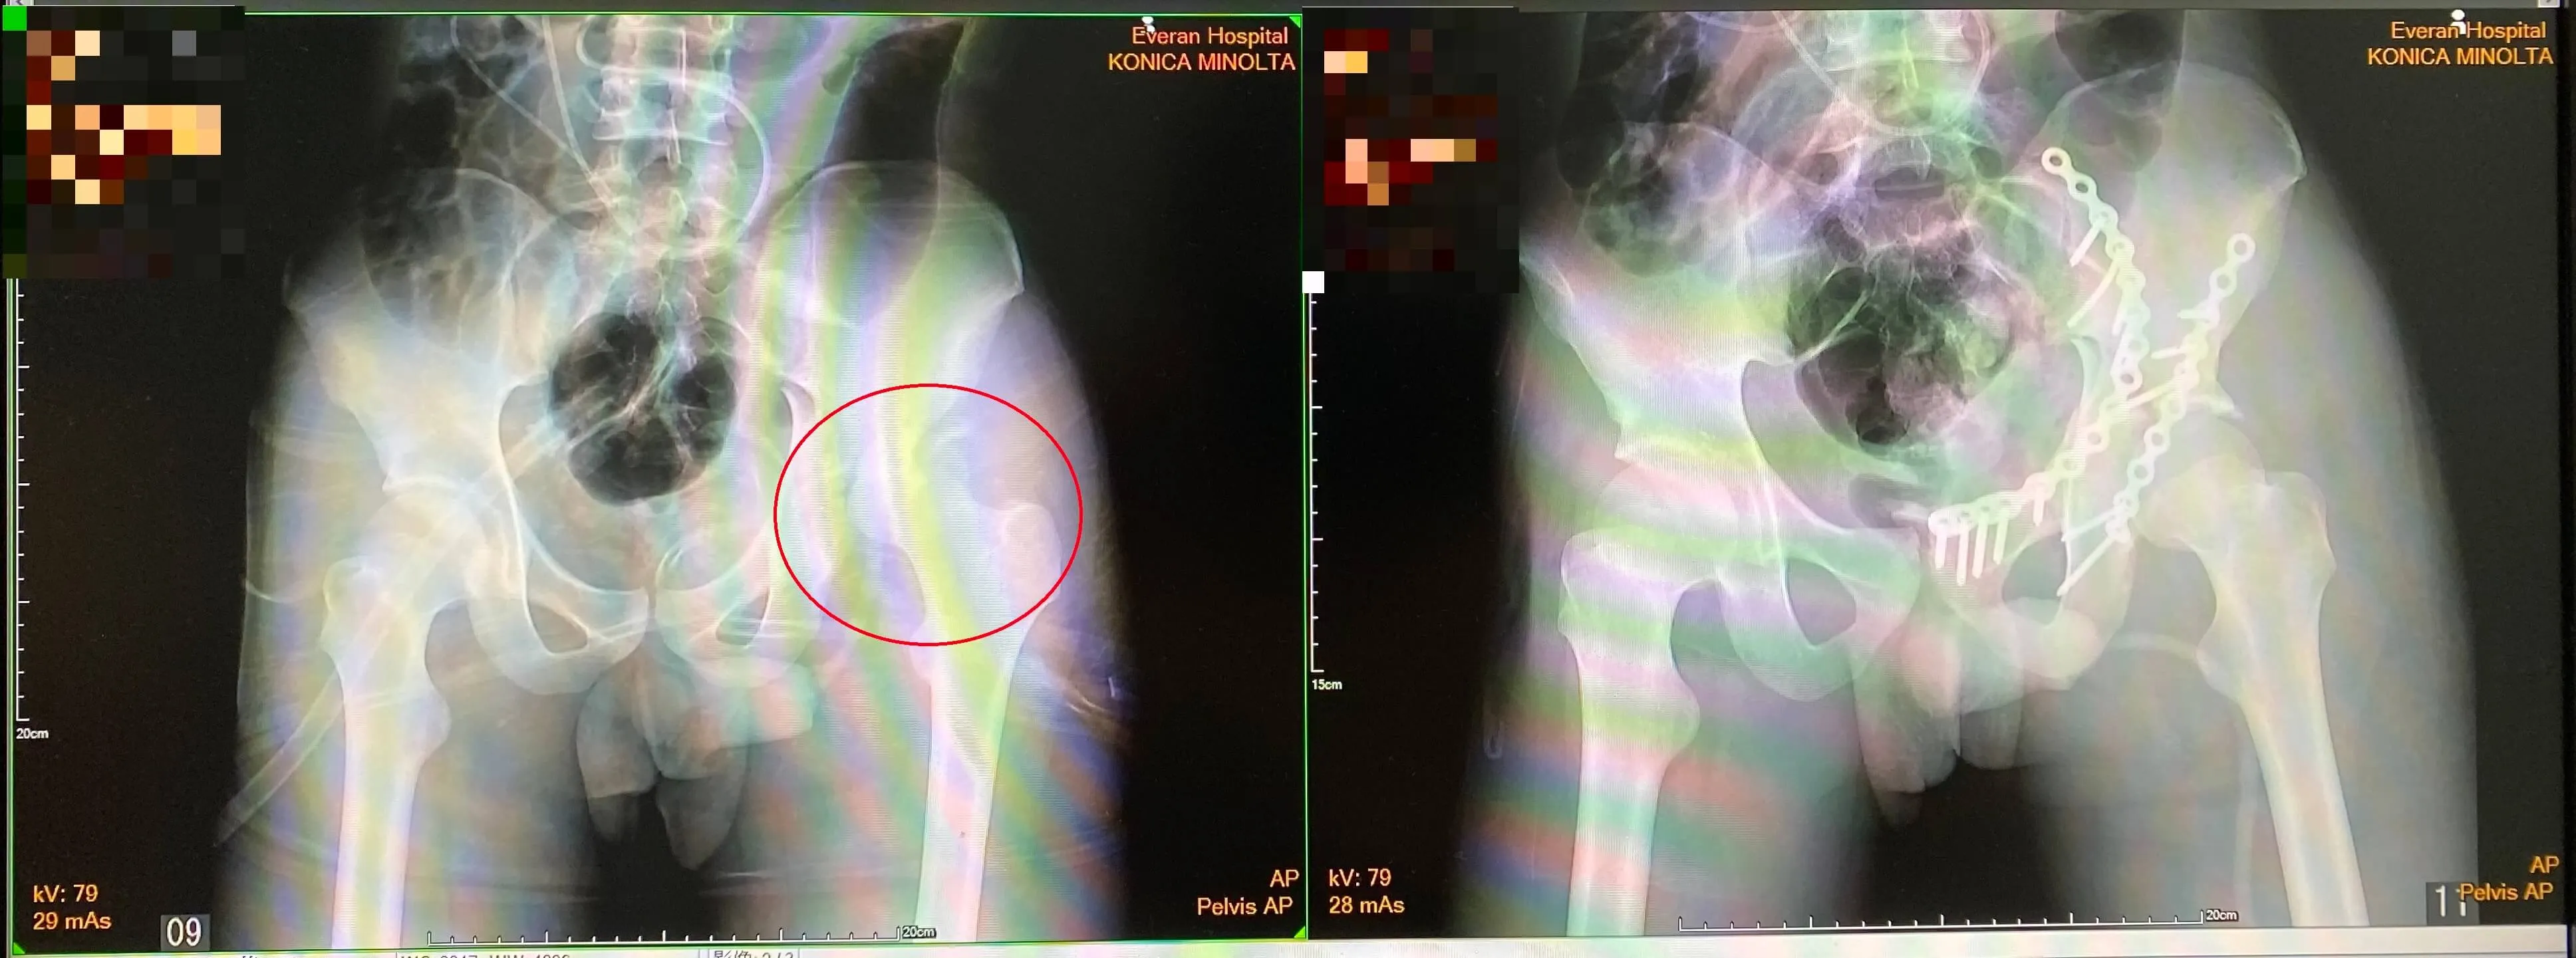

22歲張先生騎機車發生車禍,拋飛後倒地無法動彈,救護車送到急診,X光檢查發現左側髖臼骨折合併髖關節後側脫臼,長安醫院骨科團隊安排電腦斷層掃描製作3D影像重組來更精準評估骨折位置,採取微創骨折復位固定手術,傷口較傳統手術小、降低對軟組織的傷害、恢復也較快,術後疼痛及下肢活動獲得改善。

曾怡菱醫師進一步說明,骨盆為人體支撐重量和保護內臟器官的主要部位,佈滿神經跟血管,一旦骨折很容易因血管破裂引發大出血。治療方式包括保守療法及手術治療,若衝擊較小、結構仍很穩定完整,大部分可採保守治療,包括臥床休息、藥物治療等;若衝擊力道大造成裂痕或是大幅移位,則需要手術治療,張先生的髖臼骨折,由於骨折處非常不穩定,容易造成髖關節脫臼,所以需要手術治療。

因為髖臼骨折的複雜性,臨床上,會搭配高階電腦斷層檢查,精準重建3D立體影象來確定骨折詳細狀況,手術採取微創骨折復位固定術。曾怡菱醫師解釋,傳統手術是沿著腹股溝切開一個連續性約20-30公分大傷口的手術方式,微創作法則是分成兩段較小傷口來處理,這樣不僅傷口可以較小、恢復比較快,更重要的是可以降低對軟組織的傷害。